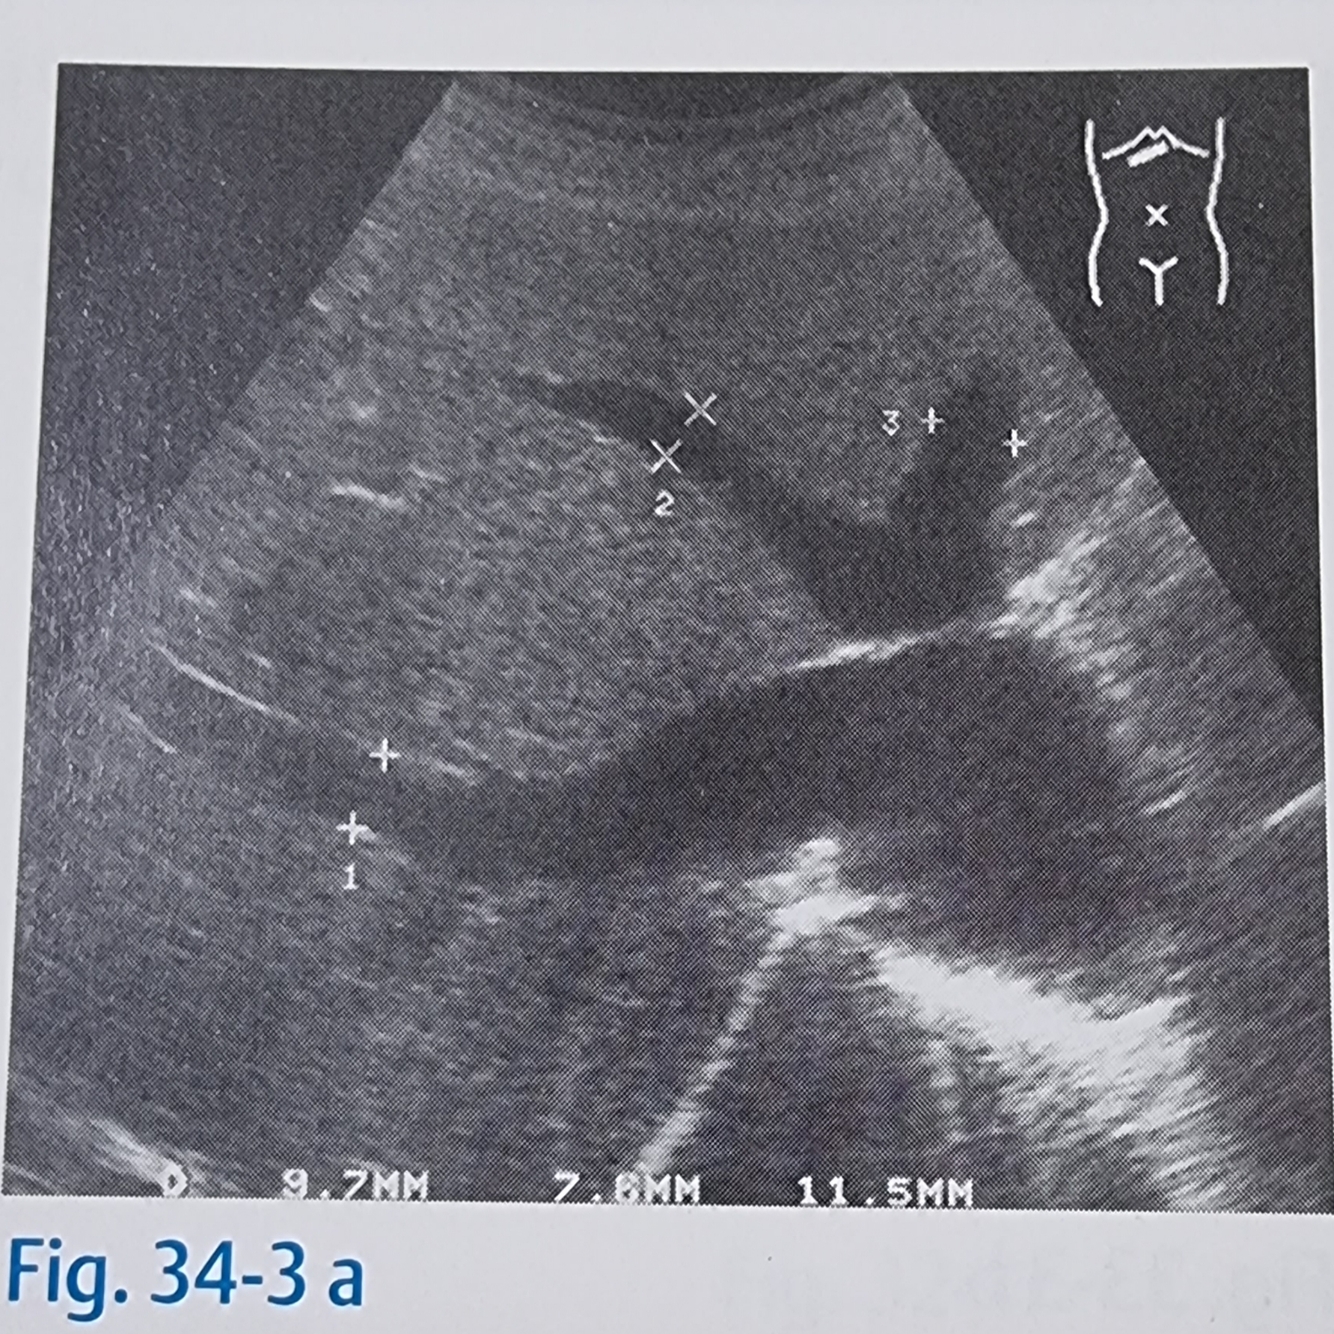

19

Q

Tumores hepáticos podem ser reconhecidos como?

A

Por sinais indiretos como o deslocamento em forma de arco das veias vizinhas

Veia hepática (10)

Tumor (54)